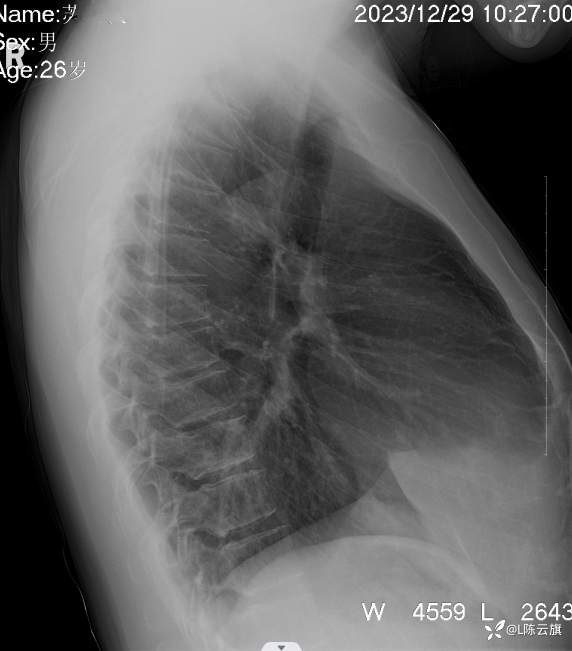

1、患者男,26岁,精神病住院患者。没有胸部及呼吸系统症状。正侧位胸片考虑什么?第一 次拟肺炎治疗后复查无改变!

2、平片所见:(CT随后上传!)